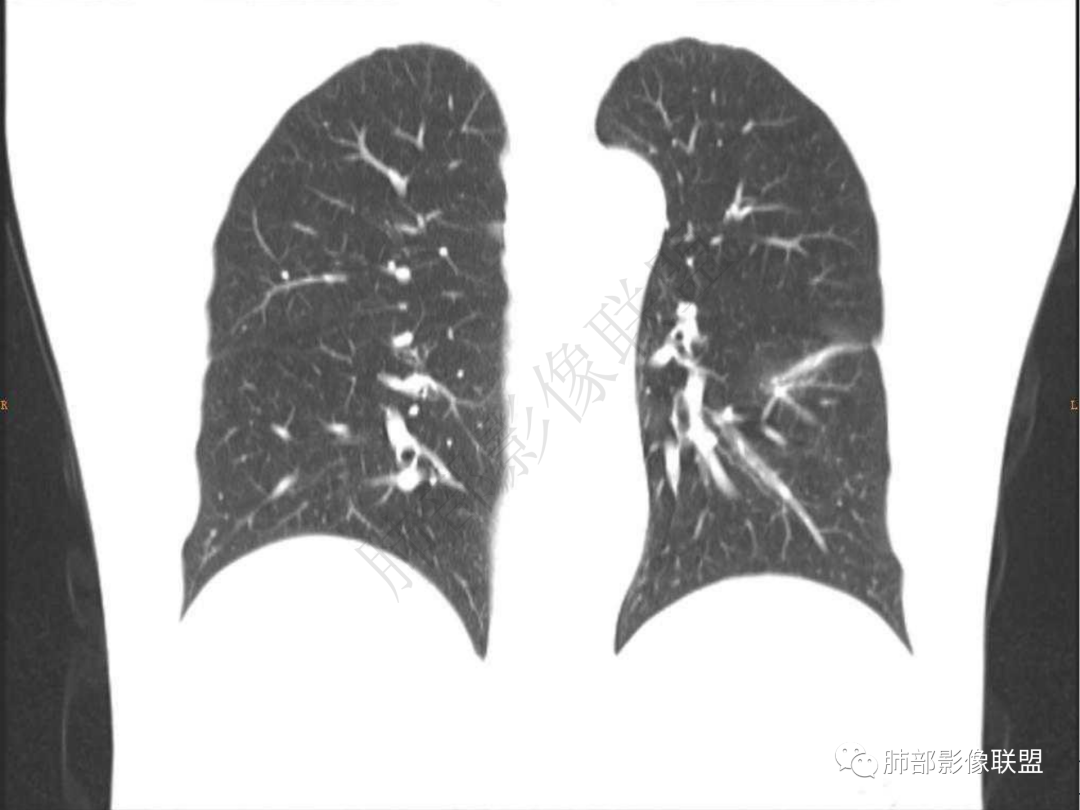

1.中年男性,咳嗽咳痰20余天,间断咯血2周

2.左肺下叶团片影,跨背段及内前基底段,实性部分类椭圆形,密度不甚均匀,可见毛刺及棘状突起,未见典型分叶及胸膜凹陷。病灶上下缘可见相应肺段支气管旁进侧出,管壁轻度增厚,未见狭窄阻塞。

3.周边较大范围磨玻璃影,边界相当模糊,小叶增厚明显。注意叶裂另一侧、左肺舌段亦可见磨玻璃影及增厚的小叶间隔。未见明确卫星病灶。

4.实性部分不均匀环形强化并显示一小范围低密度坏死区或空洞。较之肺窗,整体纵隔窗范围较小,提示病灶并不十分密实。抑或为不同时段图像。

5.双肺门及纵隔未见增大淋巴结。未见胸腔积液。